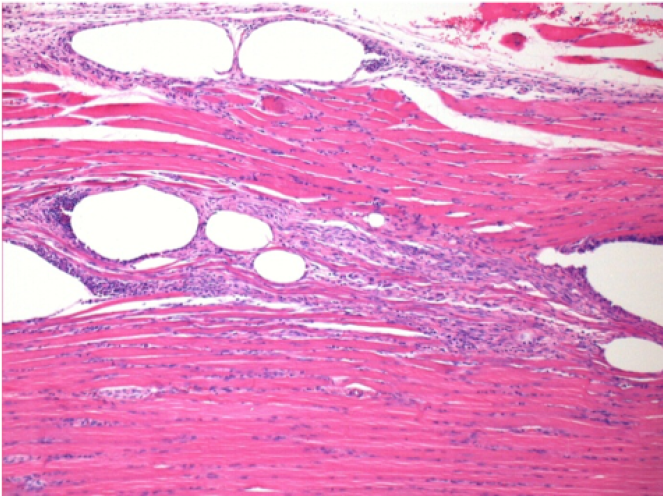

10 days after Endopeel Injection 0.1ml in the right pretibial muscle.

Here you may see the formation of the vacuoles which are surrounded by lymphocytes. Vacuoles are different from tissue necrosis . The presence of lymphocytes is related to the permeability of the cell membranes.